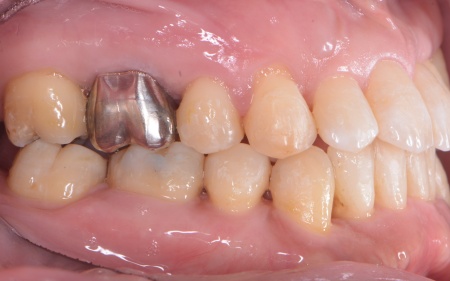

| カウンセリング | 拝見したところ、上下の歯は、ずれたりねじれたりしてデコボコに生えており、著しく歯並びが乱れていました。

またレントゲン撮影をして確認すると、右上前歯は顎の骨の中に埋まっている骨性埋伏(こっせいまいふく)の状態でした。 さらに、左下奥歯は重度の歯周病であり、歯を支えている骨が一部溶けていることが判明しました。 以上のことから、歯並びを整える矯正治療と歯周病の治療を併せて行う必要があると診断しました。 |